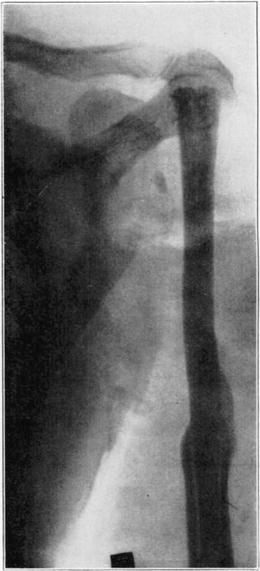

Case 5. Tibial graft thirty-nine days after insertion in humerus.

Case 5. Ten years and eight months after operation. Shows non-functioning portion of graft in medullary cavity practically unchanged, but the functioning portion above hypertrophied and transformed.